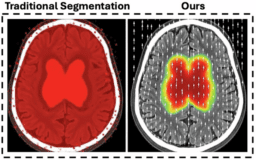

![]() | Modeling Ischemic Stroke Pathological Dynamics via Continuous Fields and Vector Flownpj Digital Medicine - (Thursday January 15, 2026) - Frequent Updates / npj Digital Medicine | |||